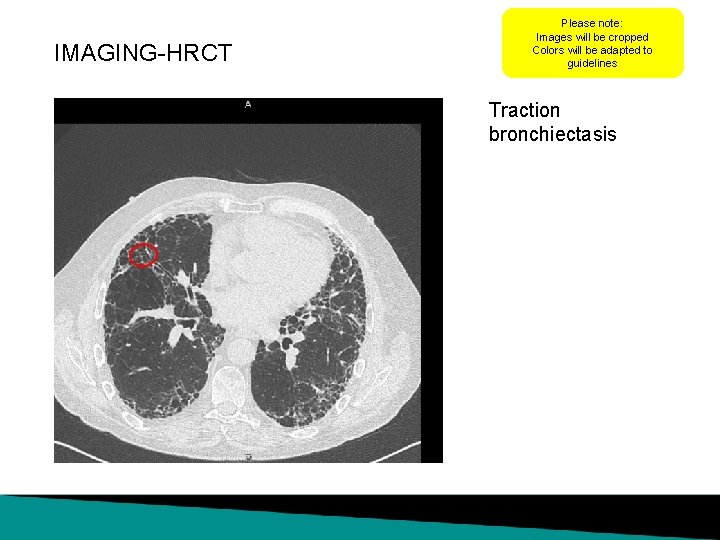

IMAGING-HRCT Please note: Images will be cropped Colors will be adapted to guidelines Traction bronchiectasis

IMAGING HRCT scan Images were obtained by thin section multislice CT (MSCT). Scan Settings • Non-enhanced scan • Window level: 1600/ • 64 -line scanner 600 • Inspiratory breath-hold • Slice thickness: 1 mm • Increment: 0. 7 mm • Scan time: 5 s The MSCT shows the following patterns: • Centrilobular emphysema • Paraseptal emphysema • Traction bronchiectasis (minimal) • Reticulation (only around emphysema)

LEARNINGS FROM THE CASE Radiologist HRCT shows a possible UIP pattern with • Traction bronchiectasis (minimal) • Centrilobular emphysema • Paraseptal emphysema / DD honeycombing • Reticulation (only around emphysema) The differential diagnosis of a UIP pattern remains difficult and sometimes cannot be “solved”. In some situations a paraseptal emphysema is very difficult to distinguish from honeycombing. In these cases searching for coincidence with centrilobular emphysema could be helpful. Raghu, et al. An official ATS/ERS/JRS/ALAT Statement: Idiopathic pulmonary fibrosis: Evidence-based guidelines for diagnosis and management. Am J Respir Crit Care Med. 2011 Mar 15; 183(6): 788 -824.